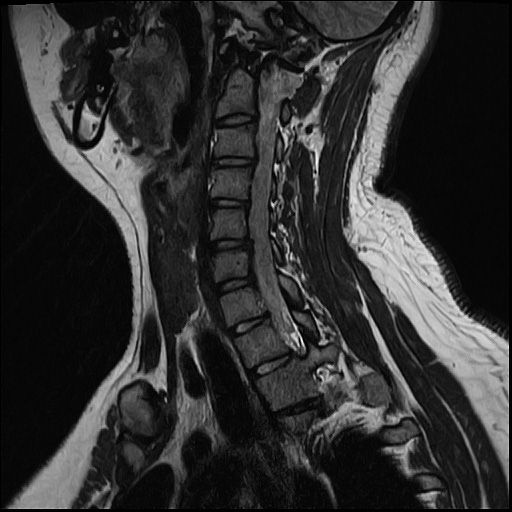

20살 허리디스크 심각한가요?

목디스크 허리디스크 둘다 가지고 있는데 목 몇번이랑 허리 몇번이 터졌고 어느정도 상태인건가요??

올리신 사진들만으로 정확한 디스크 평가가 가능하지는 않습니다. 하지만 사진의 소견들만 보았을 때에는 심하지는 않습니다.

MRI 4컷으로는 디스크 탈출의 정도를 충분히 확인이 불가능합니다.

현재 주어진 사진에서는 허리 디스크는 확인이 가능한 상태이며 그 중등도는 명확히 확인이 어렵습니다.

현재 mri에서는 디스크가 돌출된 부분이 확인됩니다. 디스크가 돌출되었다고 반드시 수술적 치료를 하는 것은 아닙니다. 디스크는 재흡수 되는 경우도 많기에 보존적 치료를 하면서 경과를 보실수 있습니다. 다만 증상이 너무 심하거나 보존적 치료에도 호전이 되지 않는다면 시술이나 수술적 치료를 고려할수 있습니다.